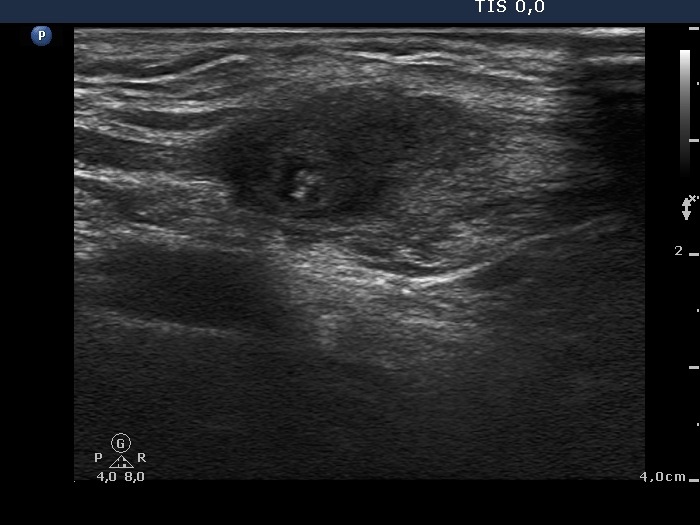

Eleven years after surgery (second and third rows of images):

Ultrasonography. The right lobe remained unchanged. Compared with the previous finding, a much smaller, inhomogeneous mass was found according to the left lobe. A few centimeters above and ventral to the left lobe, a cystic lesion was found within the strap muscle and close to this, an amorphous hyperechoic fragment was also present (see video).

1. A granulation around surgical thread can appear even decades after the operation. This was not a typical presentation but cytology was decisive.

2. While this lesion tends to appear relatively suddenly, it tends to disappear much more slowly over the years, very often lasting for up to a lifetime.

3. I cannot prove but it seems to be logical that the cystic mass seen at the second visit within the sternocleidomastoid muscle, is also a form of this granulation.